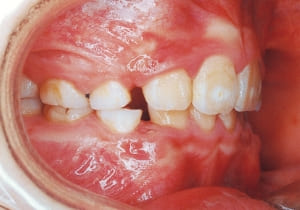

3 Initial Visit 2-11-’88

4 Initial Visit 2-11-’88

The Class II condition is pronounced, with a significant overjet of 12.5 mm(3). Although the teeth size are large, crowding is relatively mild. The maxillofacial structure has good depth and a robust bone framework(5). The mandible itself is solid , robust gonial angle, but there is significant anterior-posterior displacement relative to the maxilla(ANB 10.0°). While there is no confirmed history of thumb-sucking or similar habits, the lower lip is already pushing up against the maxillary incisors. The cause of this condition is unknown.